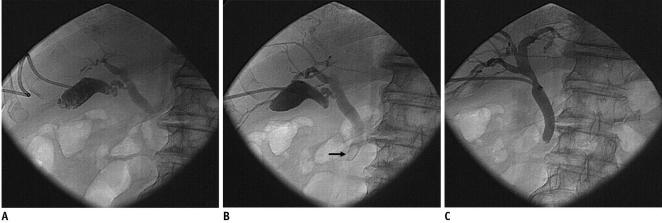

Sixty-three consecutive patients of high surgical risk with acute calculous cholecystitis underwent percutaneous transhepatic gallstone removal under conscious sedation. The stones were extracted through the 12-Fr sheath using a Wittich nitinol stone basket under fluoroscopic guidance on three days after performing a percutaneous cholecystostomy. Large or hard stones were fragmented using either the snare guide wire technique or the metallic cannula technique.

Gallstones were successfully removed from 59 of the 63 patients (94%). Reasons for stone removal failure included the inability to grasp a large stone in two patients, and the loss of tract during the procedure in two patients with a contracted gallbladder. The mean hospitalization duration was 7.3 days for acute cholecystitis patients and 9.4 days for gallbladder empyema patients. Bile peritonitis requiring percutaneous drainage developed in two patients. No symptomatic recurrence occurred during follow-up (mean, 608.3 days).